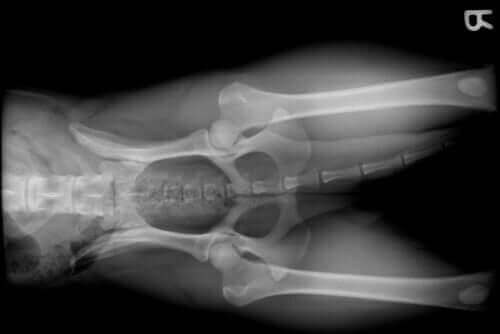

- Tür: Alman shepherd gibi bazı belli köpek ırkları, kalça çıkığı gibi problemleri yaşamaya yatkındır. Diğer taraftan, golden retriever, rottweiler veya doberman gibi büyük cüsseli ve hızlı büyüyen köpekler omuz ve dirsek çıkması gibi eklem problemlemlerini yaşamaya daha meyillidir.